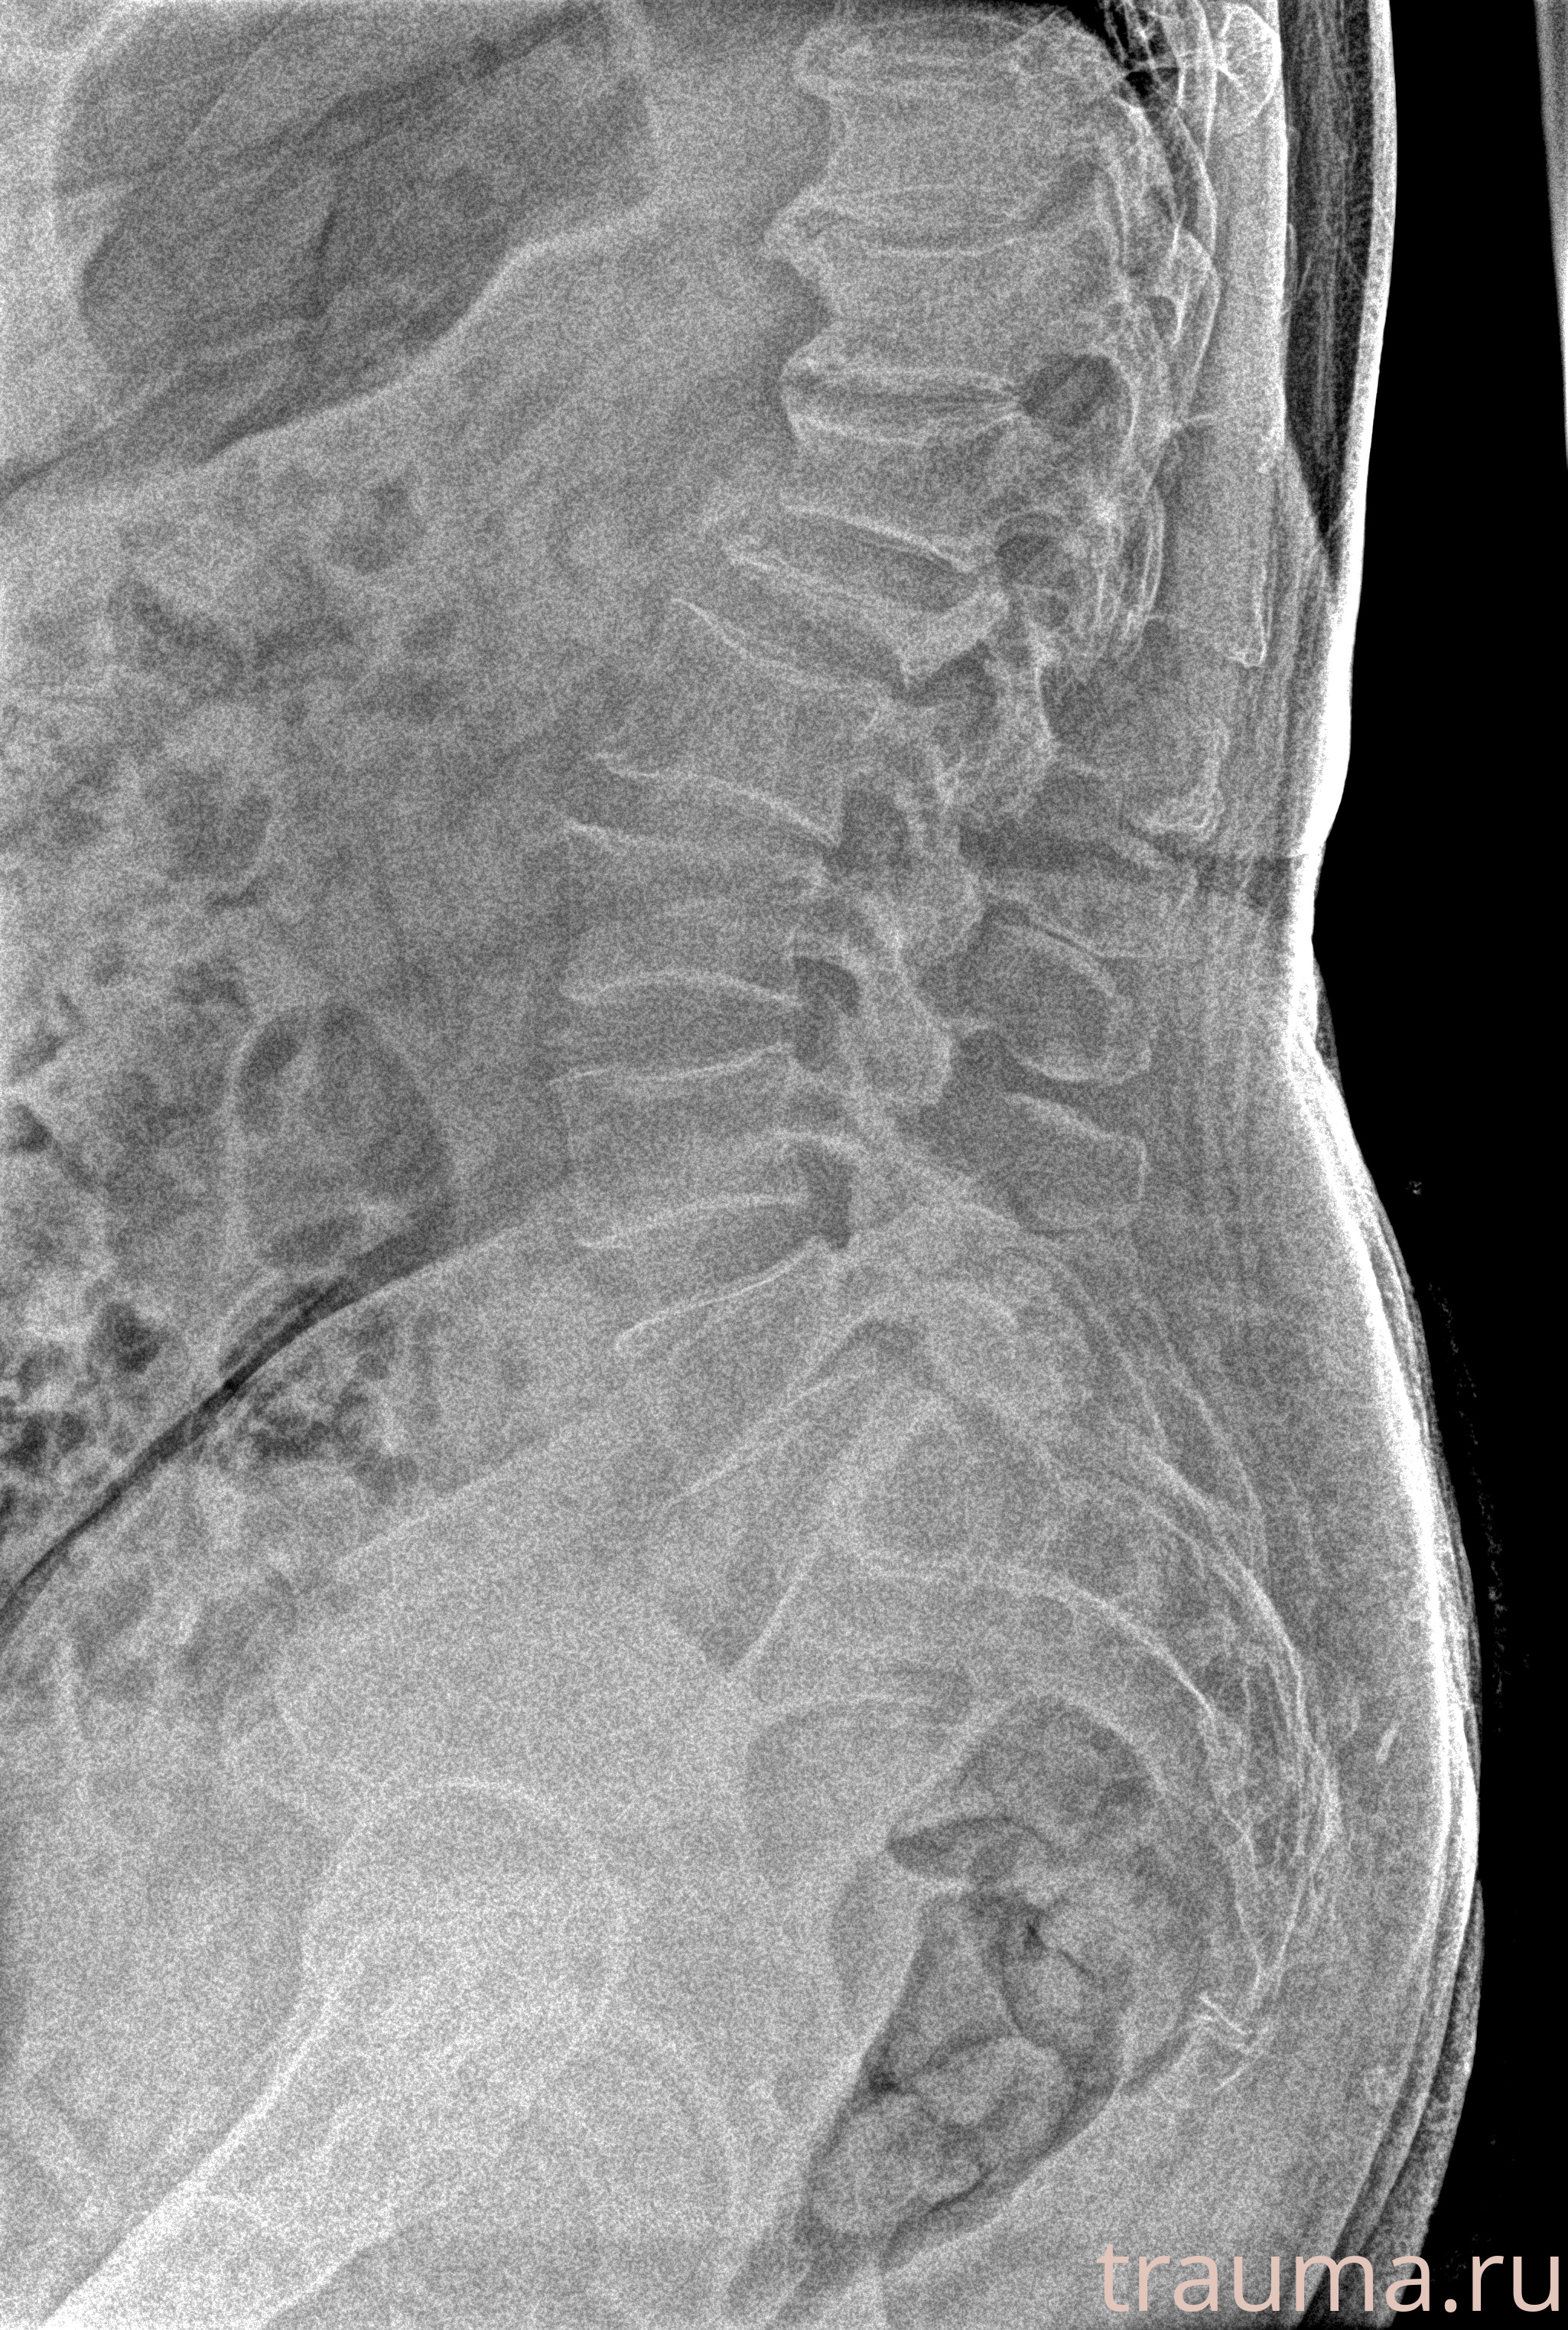

Рентгенограммы

Рентген на дому: по вашему адресу приезжает врач-рентгенолог, травматолог-ортопед с мобильным рентгеновским аппаратом, проводит диагностику травмы или заболевания, делает необходимые рентгенограммы, дает рекомендации по дальнейшему лечению. Получить качественные снимки в домашних условиях возможно благодаря уникальной методике, разработанной МосРентген Центром для института  Склифосовского